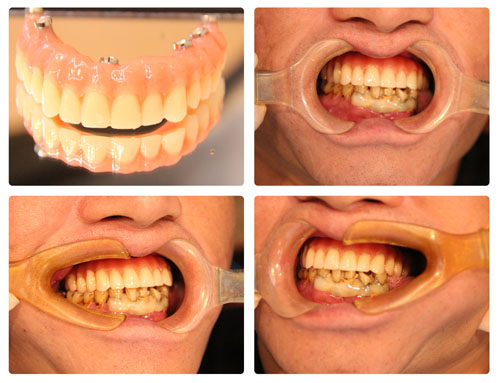

如今,种植牙越来越为人所知,但如果上下颌骨条件不佳,种植牙将非常困难,不仅要大量植骨,而且等待的时间也延长。9月26日,贝臣齿科通过高难度“穿颧种植术”,在一天内为一名患者成功种上了半口牙。

44岁的刘先生,较大的苦恼就是牙齿的缺失,牙槽骨严重萎缩低平,连活动假牙都没法戴稳。年轻时随便啃苹果,现在把水果削成块吃起来都很困难。口腔健康没了,个人心情、生活质量都受到极大影响。

种植牙是缺失牙的常规修复手段,刘先生咨询了多家医院,很多医生对他的口腔状况都束手无策。并得出了一致的结论:上颌牙槽骨极度萎缩,按传统的种植方法,不仅操作难度极大,而且术后恢复比较缓慢,种植体也很容易失败。这让刘先生十分无奈。在四处打听的过程中得知,贝臣齿科国际牙种植中心团队正是国内为数不多掌握穿颧种植术的团队。经过详细的检查和问诊后,得知可以通过穿颧种植手术解决缺牙问题,让他很是欢喜。

量身定制穿颧高难度种植方案

通过术前检查的CT片以及检测结果,传统“一日得”种植术不适合刘先生,贝臣医生团队量身定制穿颧半口高难度治疗方案来帮助刘先生恢复一口好牙!穿颧种植方案就是贝臣医生团队经过分析后最终给出的治疗方案。事实上能做这一种植方案的医生“穿颧种植方案”少之又少。经过贝臣医生团队帮助刘先生实现重获新牙的愿望。